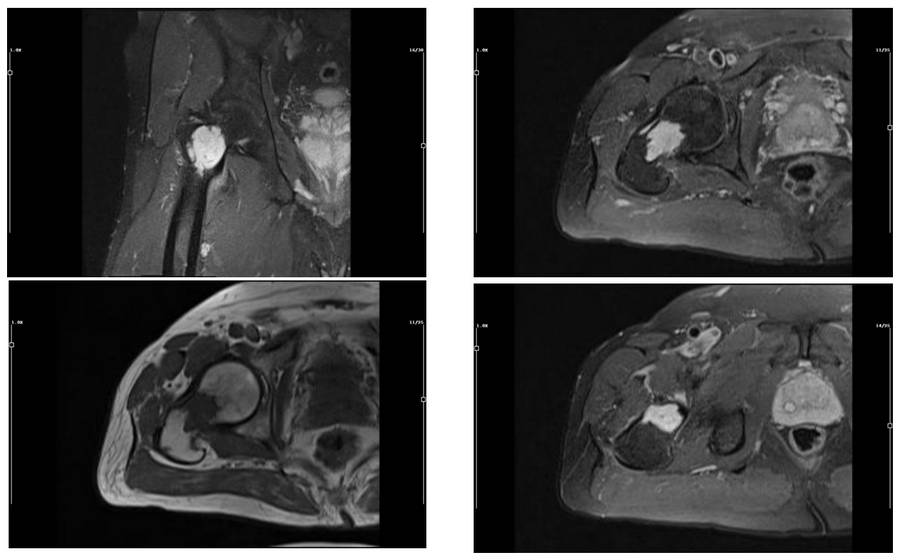

Before the surgery: Tumor on MRIsIts borders appear irregular and it shows intense contrast.